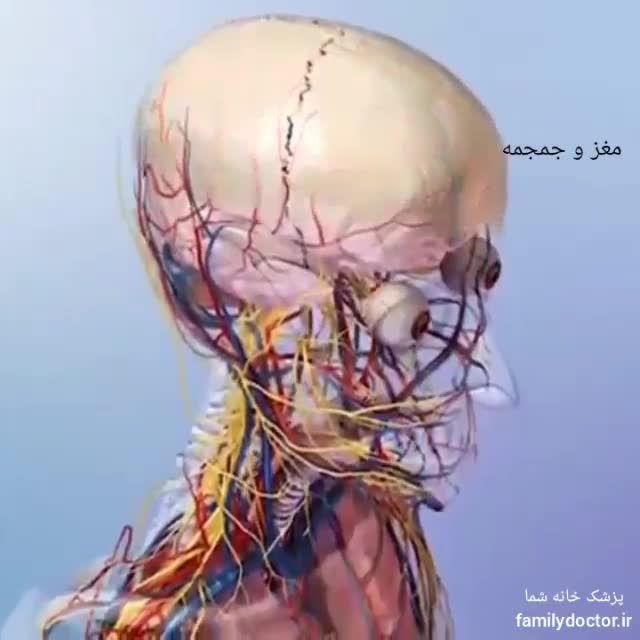

آناتومی سه بعدی بدن انسان عکس گرافی بدن.

اسکلت داربست بدن است تمام قسمت های بدن روی اسکلت قرارگرفته اند بدن انسان از ۲۰۶ قطعه استخوان تشکیل شده است این استخوان ها طوری با نظم کنار هم قرار گرفته اند که انسان را قادر می سازد حرکات دقیقی داشته باشد. استخوان یک نسج بسیار محکم است زیرا در ترکیب آن منرالها مانند کلسیم و دیگر وجود. اسکلت داربست بدن است تمام قسمت های بدن روی اسکلت قرارگرفته اند بدن انسان از ۲۰۶ قطعه استخوان تشکیل شده است این استخوان ها طوری با نظم کنار هم قرار گرفته اند که انسان را قادر می سازد حرکات دقیقی داشته باشد. آناتومی سه بعدی بدن انسان عکس گرافی بدن امعاء و احشاء بدن آناتومی سه بعدی بدن انسان عکس گرافی بدن امعاء و احشاء بدن قلب کبد روده.